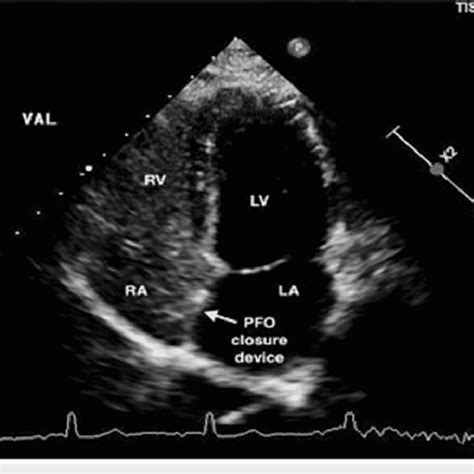

Patent Foramen Ovale | Concise Medical Knowle…

640×640

researchgate.net

Transthoracic echocardiogram with bubble study postprocedur…

A 25-mm Amplatzer PFO occluder device visualized on …